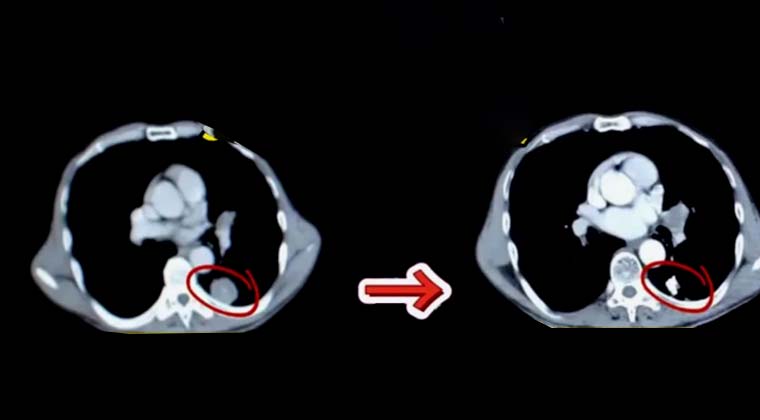

② Случай 2:

Пациент, 75 лет, рак лёгкого

После оценки выполнена имплантация частиц I-125 под контролем визуализации.

Очаг до лечения примерно 4×4 см.

Контроль через ~50 дней после лечения показывает значительное уменьшение очага, в исходной области опухоли измеримых образований не обнаружено.

Пациент 75 лет с раком лёгкого, полное исчезновение опухоли через 50 дней после имплантации частиц I-12

До лечения:

Опухоль 4×4 см

После лечения:

Полное исчезновение опухоли